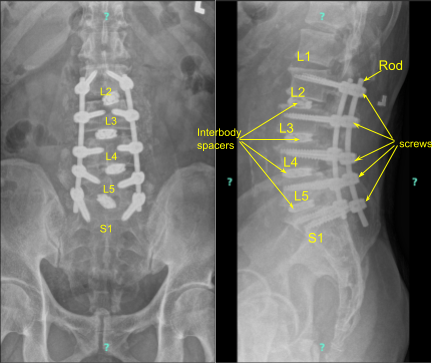

The navigation was brought in and CT scan was performed. After the navigation was verified, pedicle screws were put on both sides of L2 to S1 sequentially under navigational guidance after using gear shift, tapped and checked every time with a ball tip probe.

Acceptable positions were achieved on all the levels. The screwdriver tip was broken on the right S1 screw, but was left in situ because it was difficult to get it out and would have led to loosening.

The rods were put onto the pedicle screws and tightened in place with set screws and final tightening with the use of torque lifting screwdriver. Final pictures were taken and found to be in acceptable position.

Neuromonitoring was intact throughout the procedure. Final CT scan was also performed to check the position of cages and the screws and were found to be in acceptable position. After the closure, the patient was extubated and moved to recovery in a stable condition.